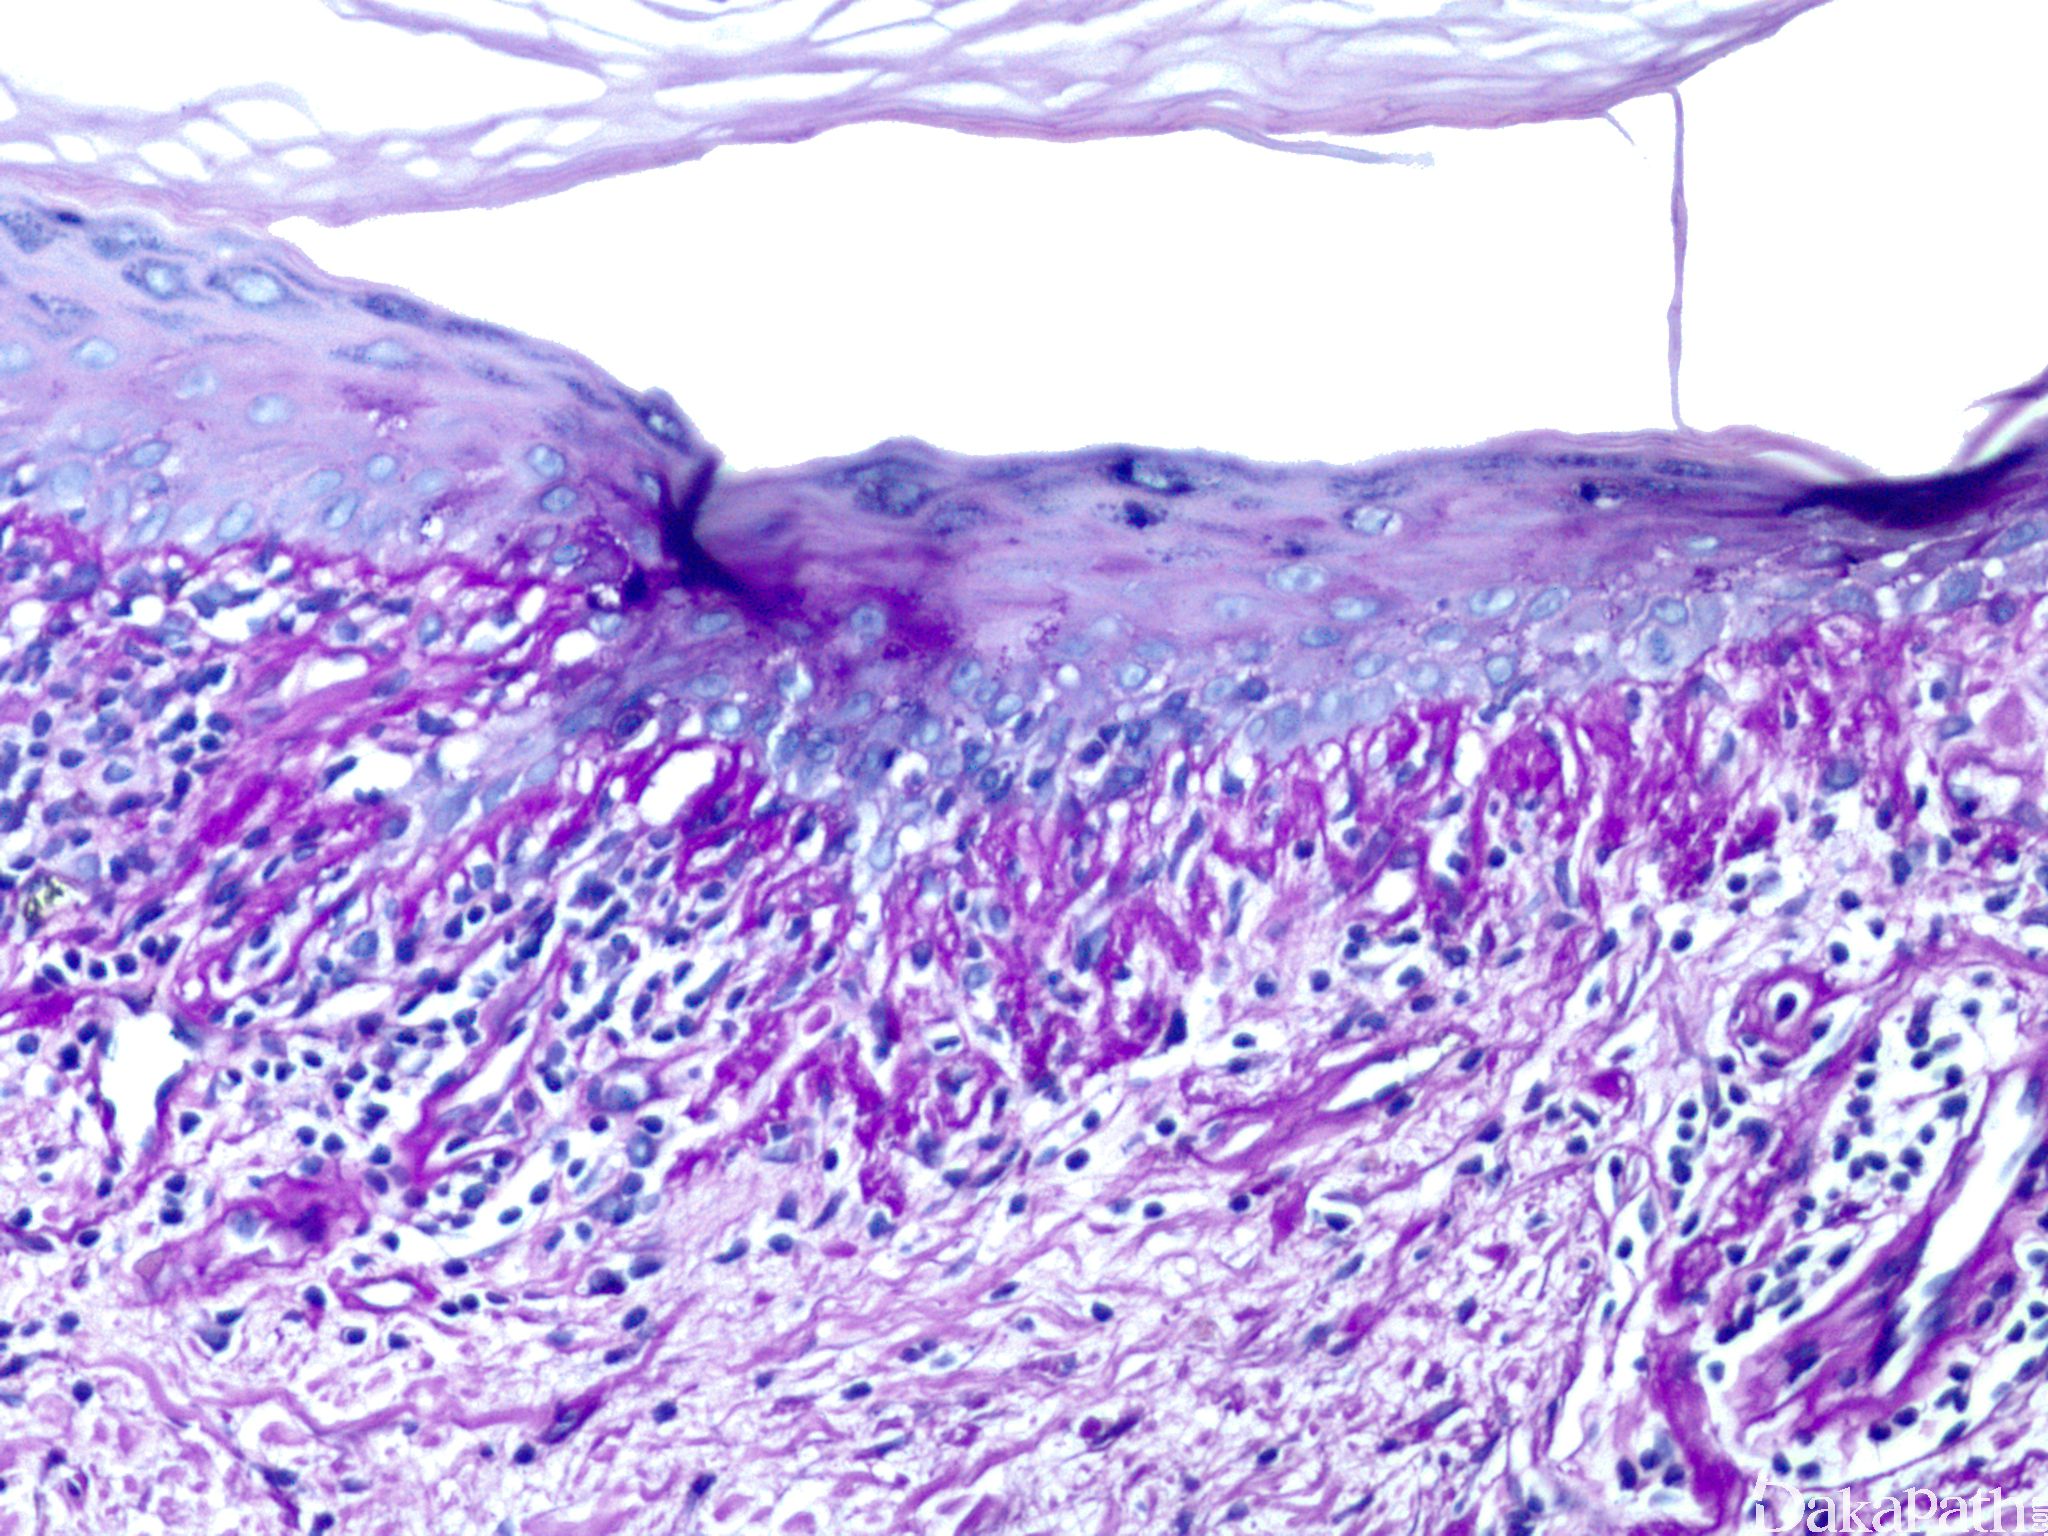

组织学改变:

表现为界面皮炎,伴有单个角质形成细胞坏死及表皮真皮交界处空泡化改变。可见致密或板层状正角化过度,表皮常萎缩。

在急性、亚急性、新生儿及早期盘状红斑狼疮中,真发内淋巴细胞稀疏浸润,可见空泡化改变,多累及真皮浅层。

充分发展的皮损表现为真皮浅深层血管、毛囊及附属器周围中等密度的淋巴细胞浸润,常无嗜酸性粒细胞。出现浆细胞及间质间酸性黏多糖(黏液)增加具有特征性。有时可见纤维蛋白栓子。表皮下及皮下可见淋巴细胞来源的核碎屑。

盘状皮损有毛囊角栓和基底鳞化(见扁平苔藓),并可出现乳头状或疣状表皮增生。

在急性、亚急性和慢性盘状红斑狼疮中基底膜常增厚。